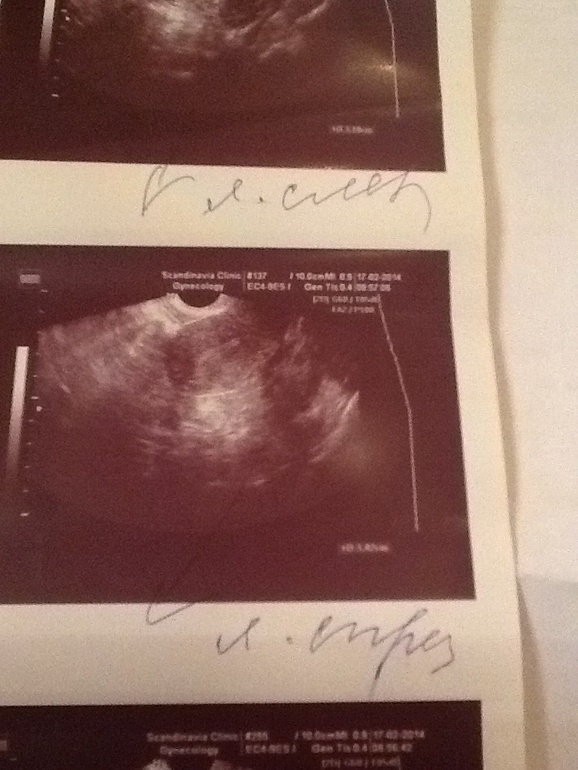

Девочки!на 22 дц(вчера)из 30,была у г,она посмотрела и сказала,что цикл пролетный скорее всего,поэтому с завтрашнего дня начинать колоть прогик через день,чтобы м начались без задержки,так как я записана на гсг на 10/03...но ведь бывает же такое,что вдруг получилось??или на 22 дц гиня явно видит,что о не было и зачатие невозможно??узи делали,но без описания...только сказала эндик хороший,а яичники как всегда(((ваше мнение,девочки,колоть??

Оль на узи былобы видно жетое тело после разрыва фоликула это еслиб О была, еслиб ее не было но намечалась то былобы видно зреющие фоликулы. К сожалению я не вижу не того ни дркгуго, есть сто-то похожее на зреющий фоликул в левом яичнике, но он настолько нечетки что скорее всего он и не развивался(( похоже что о не было и не будет(((

В том то и дело,что нет,там в кабинете у г стоит мини аппарат узи,она по нему смотрит,руками не смотрела вообще,но так как у меня стоит СПКЯ,видимо это не обсуждается,что вдруг может быть б(так обидно..по ощущениям и яб сегодня 5-6 дпо..